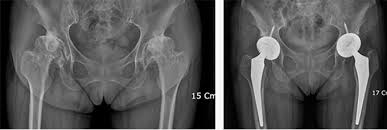

- 고관절 전치환술(Total Hip Arthroplasty, THA): 골관절염이나 류마티스 관절염, 골절 등에 널리 사용되는 방식으로, 관절 전체를 인공 관절로 교체합니다.

- 반치환술(Hemiarthroplasty): 대퇴골 두부 골절 등 특정 상황에 고관절 반만 인공으로 바꿔주는 방식입니다.